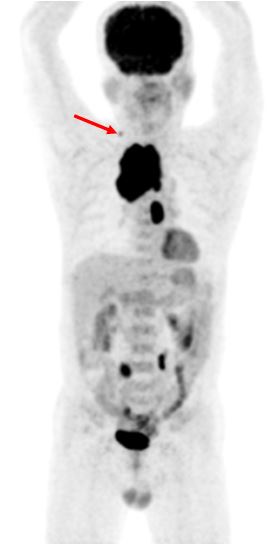

- Hình ảnh PET/CT:

Kết quả PET/CT: Hình ảnh khối u thùy trên phổi phải (mũi tên đỏ) kích thước 5,6x6,9x9,0cm, tăng hấp thu F-18 FDG, max SUV=13,18, chèn ép làm hẹp lòng khí quản, hạch lớn trung thất tăng hấp thu F-18 FDG. Tổn thương đốt sống D2 (mũi tên vàng) tăng hấp thu F-18 FDG, max SUV=8,85. |

Chẩn đoán xác định:Ung thư phổi phải di căn hạch trung thất, di căn xương, giai đoạn IV (T3N2M1). Giải phẫu bệnh: ung thư biểu mô vảy.